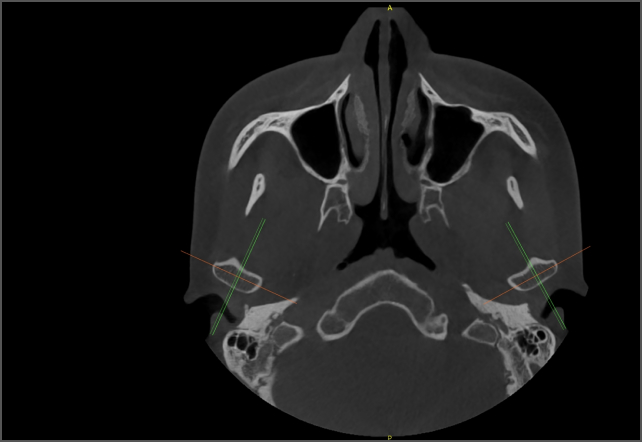

AI 加持,事半功倍 兰台医令的阅片软件包含 AI 神经管绘制、AI 气道分析、AI TMJ分析、AI 牙弓曲线、AI 正畸头影测量等智能图像处理功能,可大大提高诊断效率,实现更好的医患沟通,让医生事半功倍。